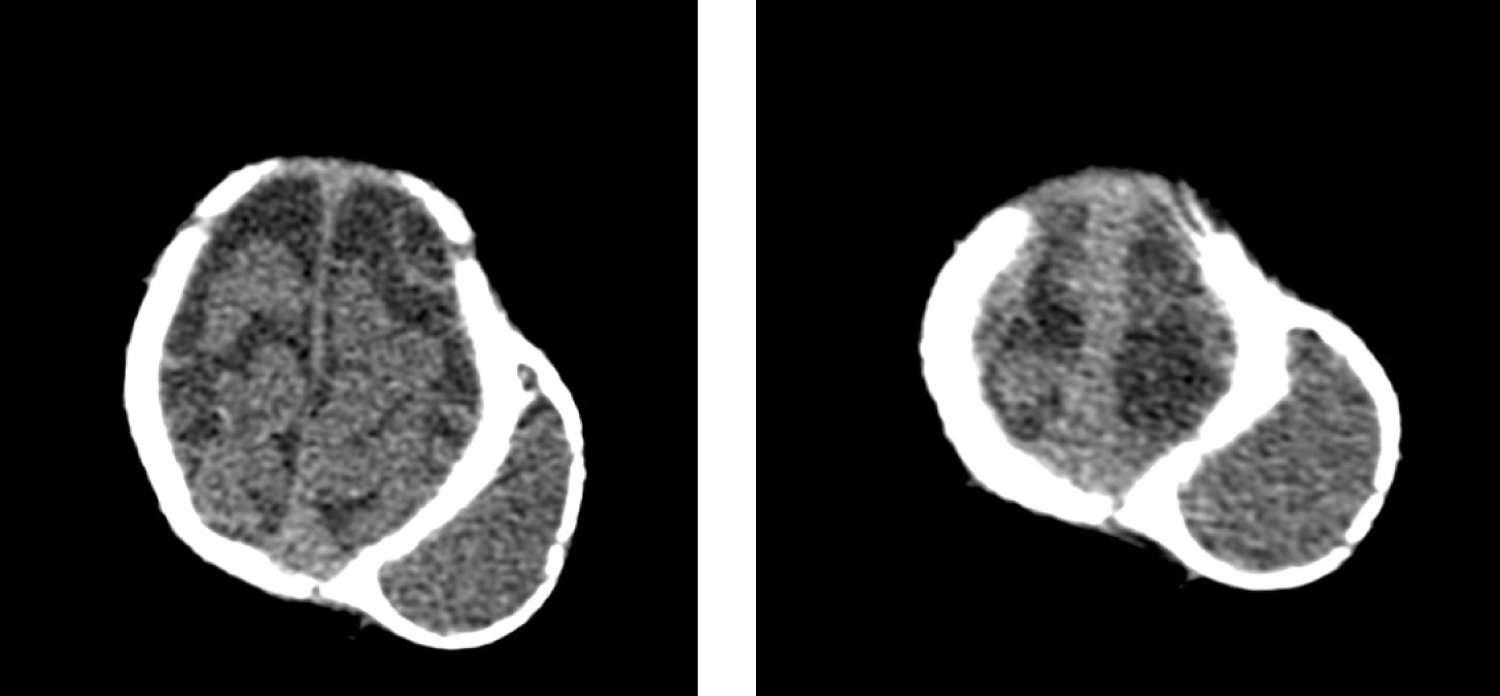

ACT scan showed left parietal extracranial hypodense mass surrounded with bone density Shell (Figure 1). This apperance is well known as double skull and is charaeteristic for the ossified cephalhemotoma. The contour of the skull is normal. Excision of new bone was planned but the parents of the patient refused the surgery.

Figure 1: A CT scan shows left parietal extracranial mass with bony shell. A double skull appearance is seen. View Figure 1